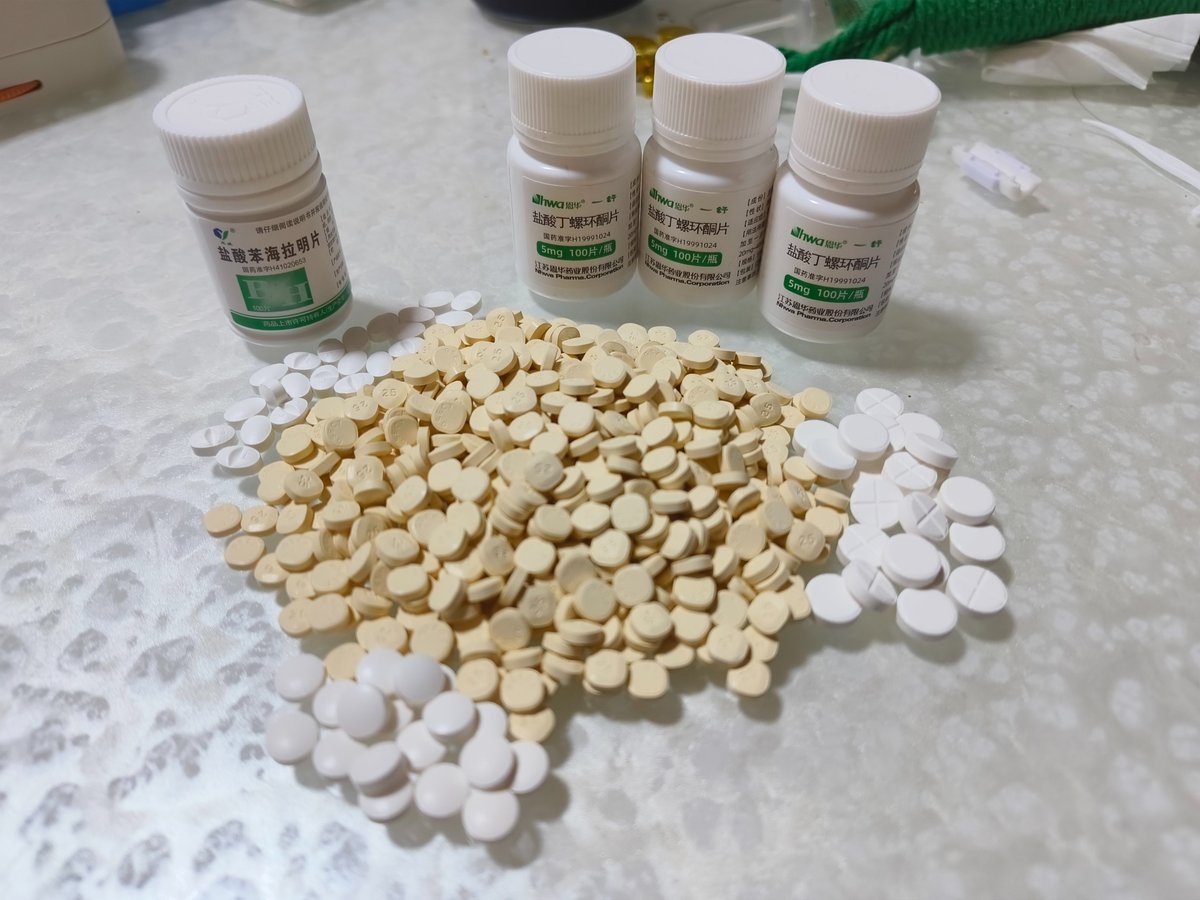

今天起来特别晕,完全不知道是怎么回事,以为是昨天测试物质的副作用我在想这么恐怖,然后怀疑今天是不是丁螺环酮吃了两次,直到我去看用药记录。。

好家伙唑吡坦又骗我吃药了还顺带上了个失忆状态,这下子知道是谁干的了。吃auv之后dxm清除得特别慢...让我感觉要从此告别了的程度,加上我基因检测本来cyp2d6就是中速代谢,这个尾巴就被拖的特别长